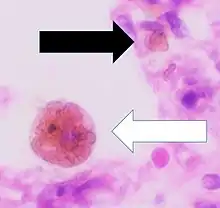

Cytology of a macrophage with typical features. Wright stain. | |